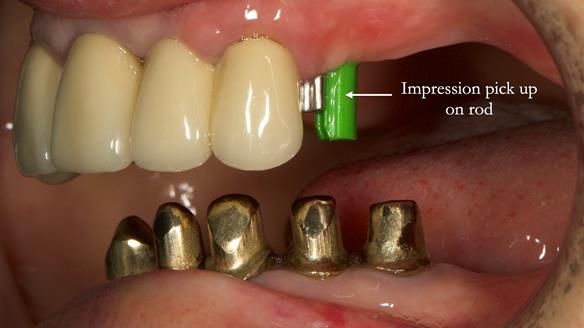

Replacement lower overdenture & upper RPD for Jackie

This Newsletter show Jackie’s case from start to finish – a technically demanding case involving replacing a telescopic crown-supported lower overdenture and an upper precision attachment-retained partial denture.

The real challenge was the lack of space for the lower overdenture.